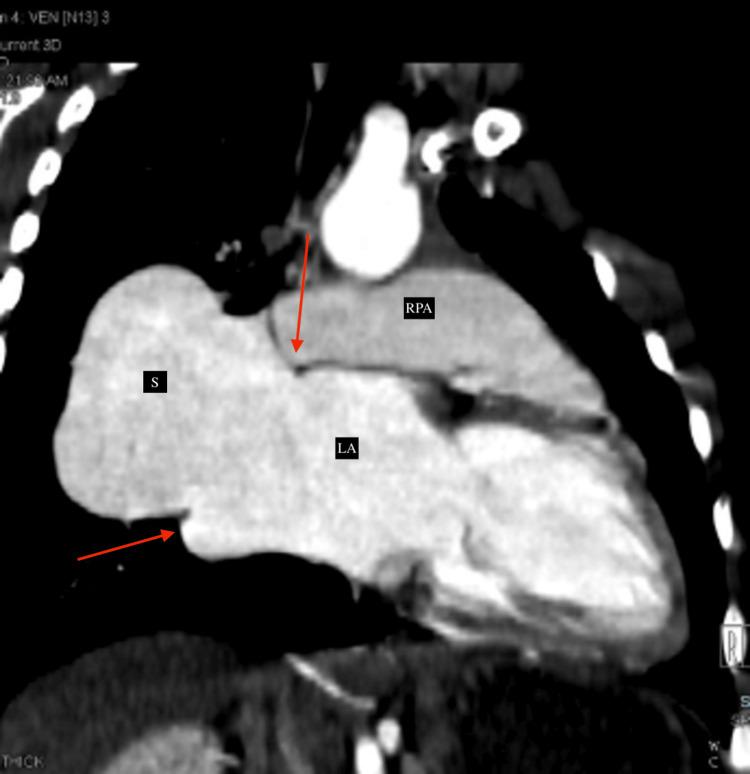

The pulmonary artery-to-left atrium (LA) fistula is one of the rare and unique structural causes of silent cyanosis. This correctable abnormality can be identified by having a high index of clinical suspicion and appropriate investigations using echocardiography and cardiac computed tomography (CT). We report an eight-year-old child who had worsening exertional dyspnea, long-standing central cyanosis, and recurrent infections. A large-sized fistula connecting the right pulmonary artery (RPA) to the LA with all the right- and left-sided pulmonary veins showed normal drainage into the LA, suggesting a type I RPA-to-LA fistula, which was diagnosed on cardiac CT. Percutaneous closure using the occluder device is planned as further management for the patient.

肺动脉至左心房瘘是导致隐匿性发绀的罕见且独特的结构性病因之一。这种可纠正的异常情况可通过高度的临床怀疑指数以及使用超声心动图和心脏计算机断层扫描(CT)进行适当检查来识别。我们报告一名8岁儿童,其劳力性呼吸困难加重、长期中心性发绀且反复感染。一个连接右肺动脉(RPA)与左心房的大型瘘管,所有左右肺静脉均正常引流至左心房,提示为I型RPA至左心房瘘,这是通过心脏CT诊断出来的。计划使用封堵器进行经皮封堵作为该患者的进一步治疗措施。